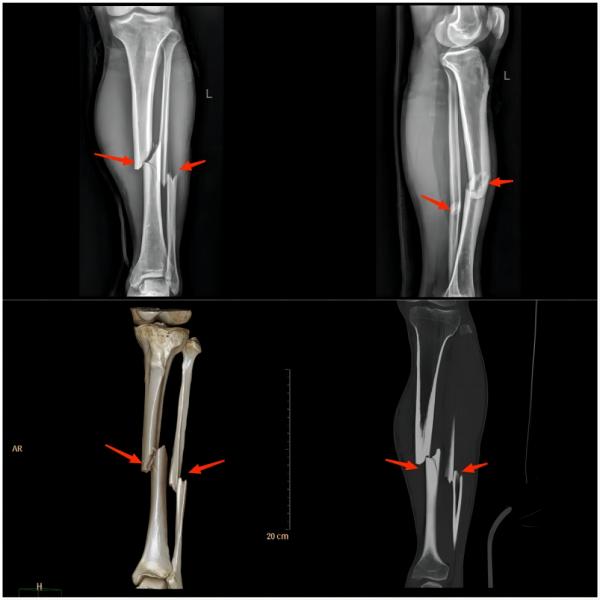

④ 小腿损伤

(上图为左胫腓骨双骨折)

常见原因:比赛的时候由于紧张地争抢、快速地跑动与铲球,常常被对手的球鞋、膝关节以及小腿踢撞,引起小腿肌肉挫伤、皮下血肿、肌肉断裂以及骨的损伤(如胫腓骨骨折)等。